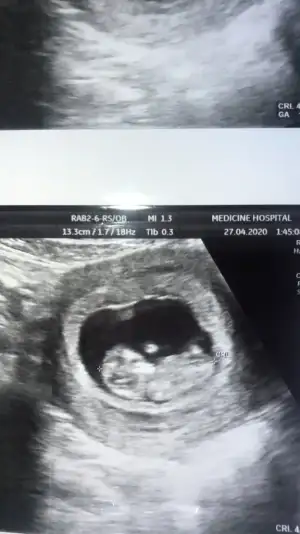

8 hafta ya göre erkek ama siz 11 12 13 hafta nub için paylaşınbize de tahmin yaparmısınız. ikisi de karından usg. ilk resim 9+4 ikincisi 8